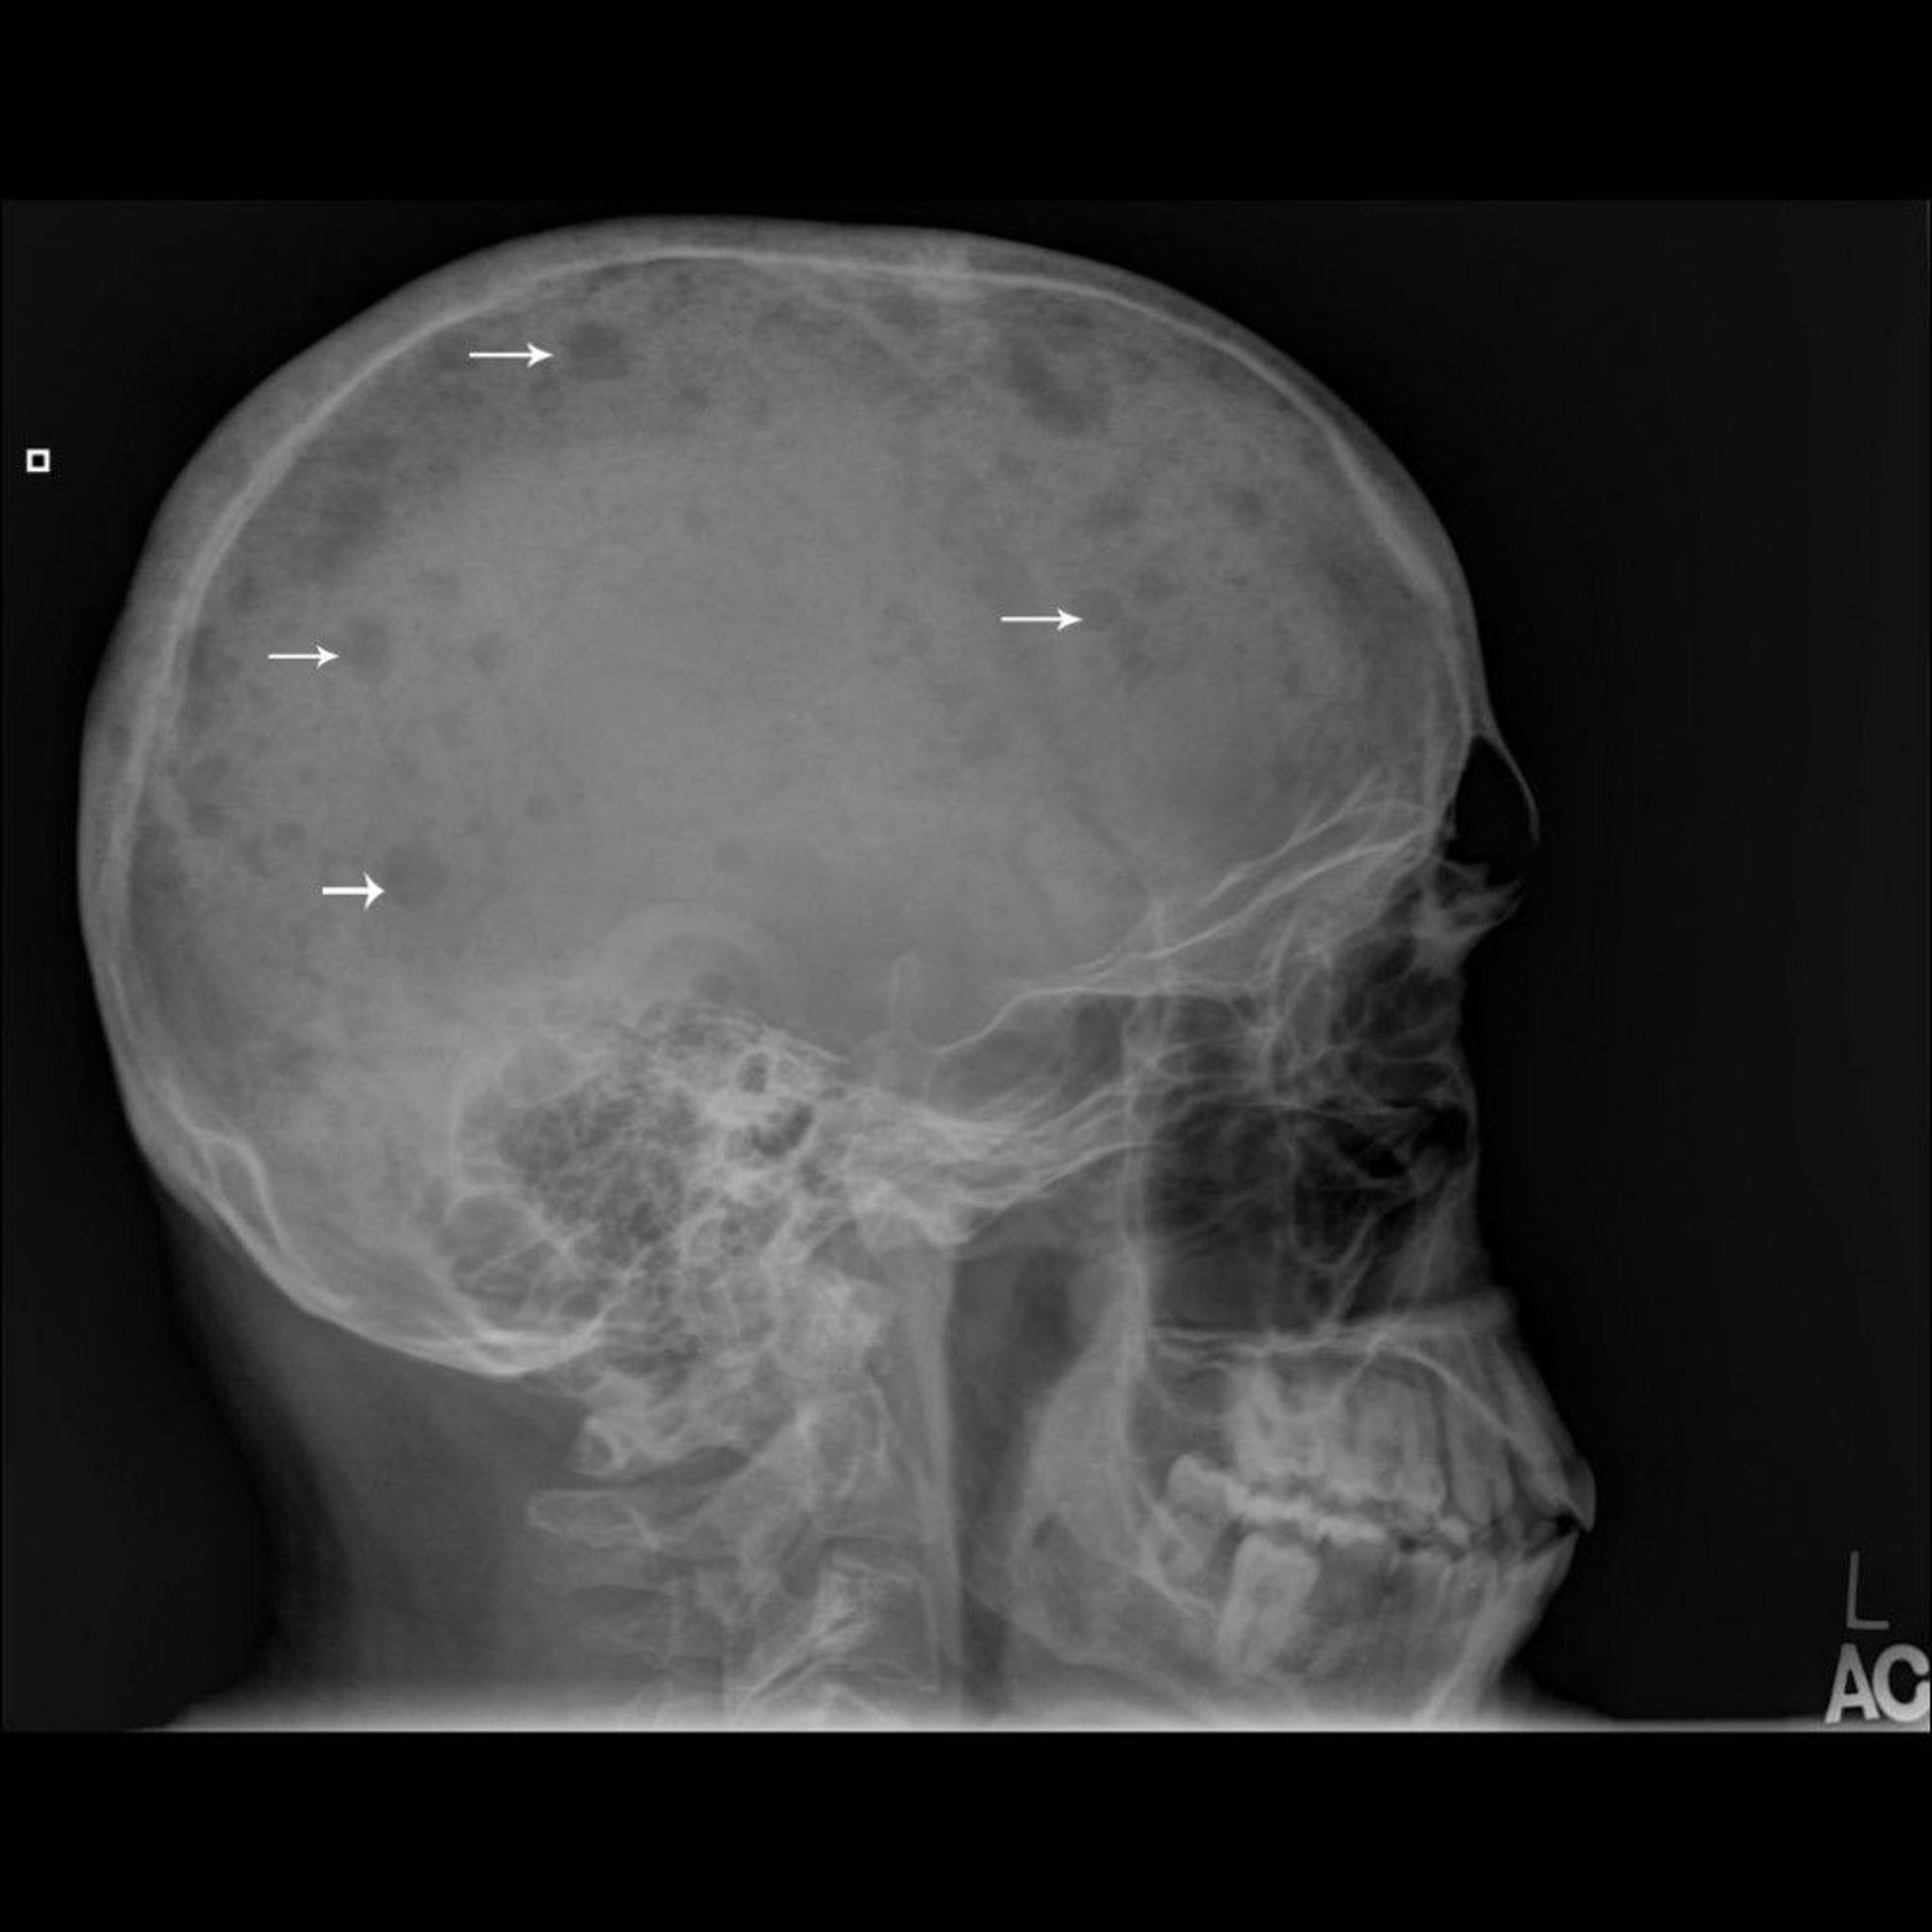

На данном рентгеновском снимке показаны множественные "штампованные"поражения кости (стрелки), которые являются типичными для множественной миеломы.

Image courtesy of Michael J. Joyce, MD, and Hakan Ilaslan, MD.